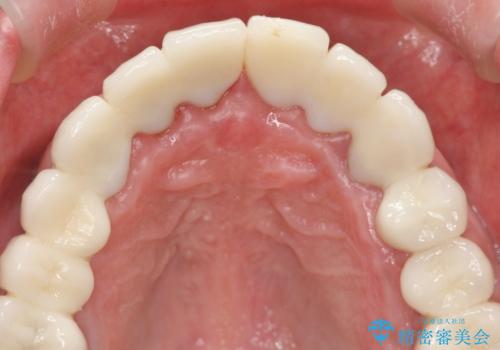

- 前医で行った前歯セラミック形態の改善、常に腫れぼったく歯ブラシの際に出血のある前歯部の治療を希望され来院されました。

前医により、前歯は歯ぐきの奥深くまで形成されこのままの状態でセラミックをやりかえたとしても歯ぐきの腫れの改善は難しい状況です。

歯周外科を行い歯と歯槽骨・歯肉の関係を是正することで歯ぐきの状態を改善し、将来に亘り安定した歯周環境の維持を期待できるセラミック治療を実践します。